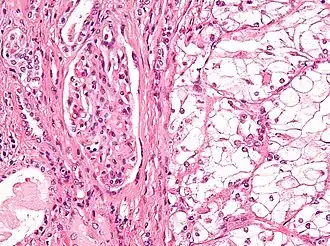

![]() Микрофотография, демонстрирующая наиболее частый тип рака почки — светлоклеточный (окраска гематоксилином и эозином) | |